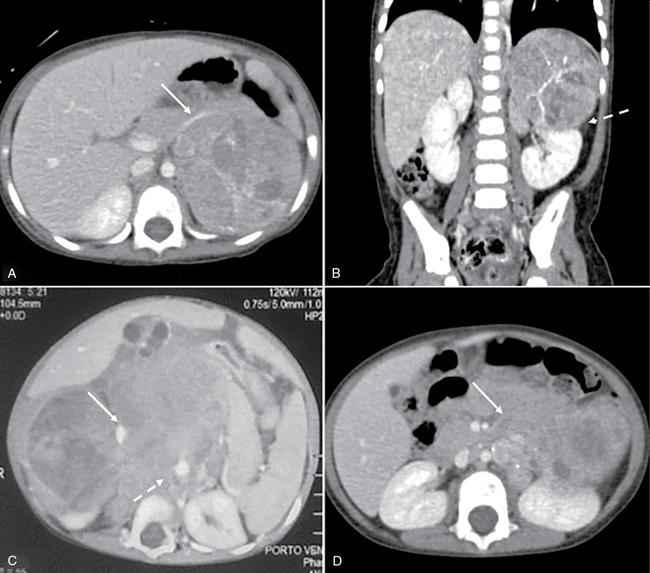

Devasenathipathy Kandasamy, Naren Hemachandran Retroperitoneal masses in children are relatively rare tumours and can primarily arise from the retroperitoneum or from any of the retroperitoneal organs (kidneys, adrenals, pancreas, duodenum, ascending and descending colon). This chapter primarily focuses on the primary retroperitoneal and adrenal masses. The spectrum of tumours affecting the paediatric age group is considerably different from those seen in the adults. The wide spectrum of diseases results in a wide range of clinical presentations which range from totally asymptomatic to even neurological symptoms in some. The presentation is usually nonspecific and imaging plays a major role in identification and characterization of these lesions. Ultrasonography is the initial modality used in children with any abdominal symptoms. Ultrasonography primarily serves three purposes. Firstly, as a screening tool for the detection of these masses, which would then be further evaluated with Computed Tomography (CT) or Magnetic Resonance Imaging (MRI), and secondly for characterizing whether a mass is cystic or solid and thirdly to localize it. CT is the workhorse in the evaluation, localization and characterization of retroperitoneal masses in children. Due to short scan times and a high spatial resolution, CT is the preferred modality in children with retroperitoneal masses. MRI in children usually requires deep sedation or general anaesthesia due to the longer acquisition time. Thus, in spite of a better contrast resolution, MRI is only used as a problem-solving tool. In this chapter, we propose a radiological algorithm for the characterization of various retroperitoneal masses in children. This is based on the primary nature of the mass and they are classified into fat containing, predominantly solid and predominantly cystic groups (Fig. 10.10.1). Various diseases have been categorized into these groups based on the most typical findings. Although not absolute, this radiological algorithm would provide a practical approach to narrow down the differential diagnosis in a child with a retroperitoneal mass. The identification of fat within a lesion considerably narrows down the differentials. The identification of intralesion fat is more easily accomplished on CT/MRI than on ultrasonography. The most common fat containing retroperitoneal lesions in a child are teratoma and lipoblastoma. Teratomas are usually complex solid cystic masses with fat and calcifications, while lipoblastomas are predominantly fat containing masses with variable amounts of enhancing soft tissue. Teratomas are the most common type of germ cell tumours in children. They can be mature, immature and mixed malignant types. Of these, benign mature teratomas are the most common and they show the presence of derivatives of all three embryonic layers – ectoderm, mesoderm and endoderm. They usually present as a painless increase in abdominal girth with a palpable abdominal lump. Imaging shows a heterogeneous solid-cystic mass with variable amount of fat and calcifications. The calcifications are coarse, chunky and well-formed bony components such as teeth are characteristic. Immature teratomas are larger, heterogeneous with or without significant fat component. Presence of haemorrhage or necrosis in a predominantly solid mass is suggestive of malignancy. Benign lesions show mass effect and displacement of the adjacent structures while invasion is typically seen in malignant ones. Other germ cell tumours are seminomatous and nonseminomatous germ cell tumours which include embryonal carcinoma, choriocarcinoma and yolk sac tumour. Primary retroperitoneal germ cell tumours (apart from teratomas) are very rare and majority of them are nodal deposits seen in a patient with a primary gonadal germ cell tumour. These are benign tumours of fatty origin (adipocytes) seen predominantly in infants and children. Lipoblastomas are well delineated, circumscribed, encapsulated lesions while lipoblastomatosis are unencapsulated locally invasive lesions. On imaging, they are almost entirely fatty with variable amounts of enhancing soft tissue components within. This group constitutes the most common retroperitoneal lesions in children. They can be subclassified into those that are diffusely infiltrative and those that are well circumscribed/encapsulated. The former includes neuroblastoma, rhabdomyosarcoma, lymphoma and IgG4 deposition disease while the latter includes ganglioneuroma, adrenocortical carcinoma, neurofibroma and phaeochromocytoma/paraganglioma. Neurogenic tumours can be classified into those of ganglion cell origin (sympathetic and parasympathetic) and those of nerve sheath origin. Tumours of sympathetic ganglion cell origin include ganglioneuroma, ganglioneuroblastoma and neuroblastoma in the increasing order of malignant potential. Tumours of nerve sheath origin can be benign or malignant. Benign nerve sheath tumours include neurofibroma and schwannoma, while their malignant counterpart is malignant peripheral nerve sheath tumour. Of these, neuroblastoma and ganglioneuroblastoma show overlapping clinical and radiological features and are described together here. Those lesions, which are the benign end of the spectrum (ganglioneuroma, schwannoma and neurofibroma), usually present as well-circumscribed lesions and are described in the next section. Neuroblastoma is the most common and the most malignant amongst the spectrum of neurogenic tumours of sympathetic ganglion cell origin. Overall, they represent the fourth most common paediatric malignancy after leukemia, CNS neoplasms and lymphoma. It is usually diagnosed below the age of 5 years (median age of diagnosis – around 16 months). Rarely they can also be diagnosed in-utero on ultrasonography or even in children above the age of 10 years. They can present with a wide range of symptoms and the degrees of symptoms are not related to the size of the tumour. The most common sites of origin of neuroblastoma are adrenal medulla (35%), primary retroperitoneum (30%) followed by posterior mediastinum (20%), pelvis/presacral space (2%–3%) and neck (1%–2%). Nearly half to two-thirds of the patients have disseminated disease at the time of diagnosis with metastasis to bone, liver, lymph nodes or skin. Primary multifocal neuroblastoma is rare and may be familial. They can be synchronous or metachronous noncontiguous tumours. On imaging, these are usually seen as large heterogeneous, diffusely infiltrative, lobulated masses with calcifications in nearly 90% of abdominal neuroblastomas. Heterogeneity is due to areas of necrosis and haemorrhage within the lesion. The lesion lacks a definite capsule and this accounts for its diffusely infiltrative nature, although relatively well-defined masses are not uncommon. Multiple large bulky nodes can be seen with characteristics similar to the primary tumour and this makes the differentiation of the tumour from the adjacent nodal mass difficult. There can be encasement of the vessels without luminal invasion. They typically insinuate around the major vessels and lift the aorta off the vertebral column. Adjacent organs like kidneys are usually displaced by the mass effect. However, they can also show direct invasion of adjacent organs and structures like psoas muscle. Intraspinal extension can be seen and is more often seen in thoracic neuroblastoma than with abdominal neuroblastoma. The International Neuroblastoma Staging System (INSS), first proposed in 1988 and modified in 1993, is still widely used (Table 10.10.1). However, it is based on the extent of tumour removal on surgery and hence cannot be used as a pretreatment staging system.

Predominantly solid lesions – diffusely infiltrative (Figs. 10.10.3 and 10.10.4)

Neuroblastoma